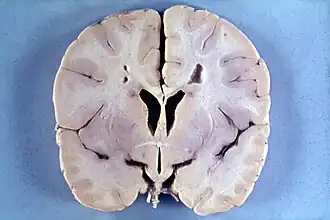

La maladie d'Alexander est une maladie rare de la substance blanche du cerveau. Elle survient le plus souvent dans les premières années de vie (forme infantile) mais parfois plus tard (forme juvénile) mais des formes néonatales ou de l'adulte existent.

Les principaux signes de cette maladie apparaissent avant deux ans et comprennent une macrocéphalie, des bosses des os frontaux, des convulsions, un retard psychomoteur progressif et une quadriparésie. Une hydrocéphalie secondaire à une sténose de l'aqueduc de Sylvius est fréquente[2]. La survie des enfants atteints se compte en mois ou en années.